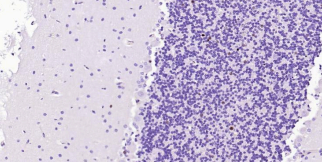

AI604895, BHLHB1, BHLHE19, Olg-2, OLIG2, OLIGO2, PRKCBP2, RACK17, RK17, bHLHe19, oligodendrocyte transcription factor 2.Validation Data